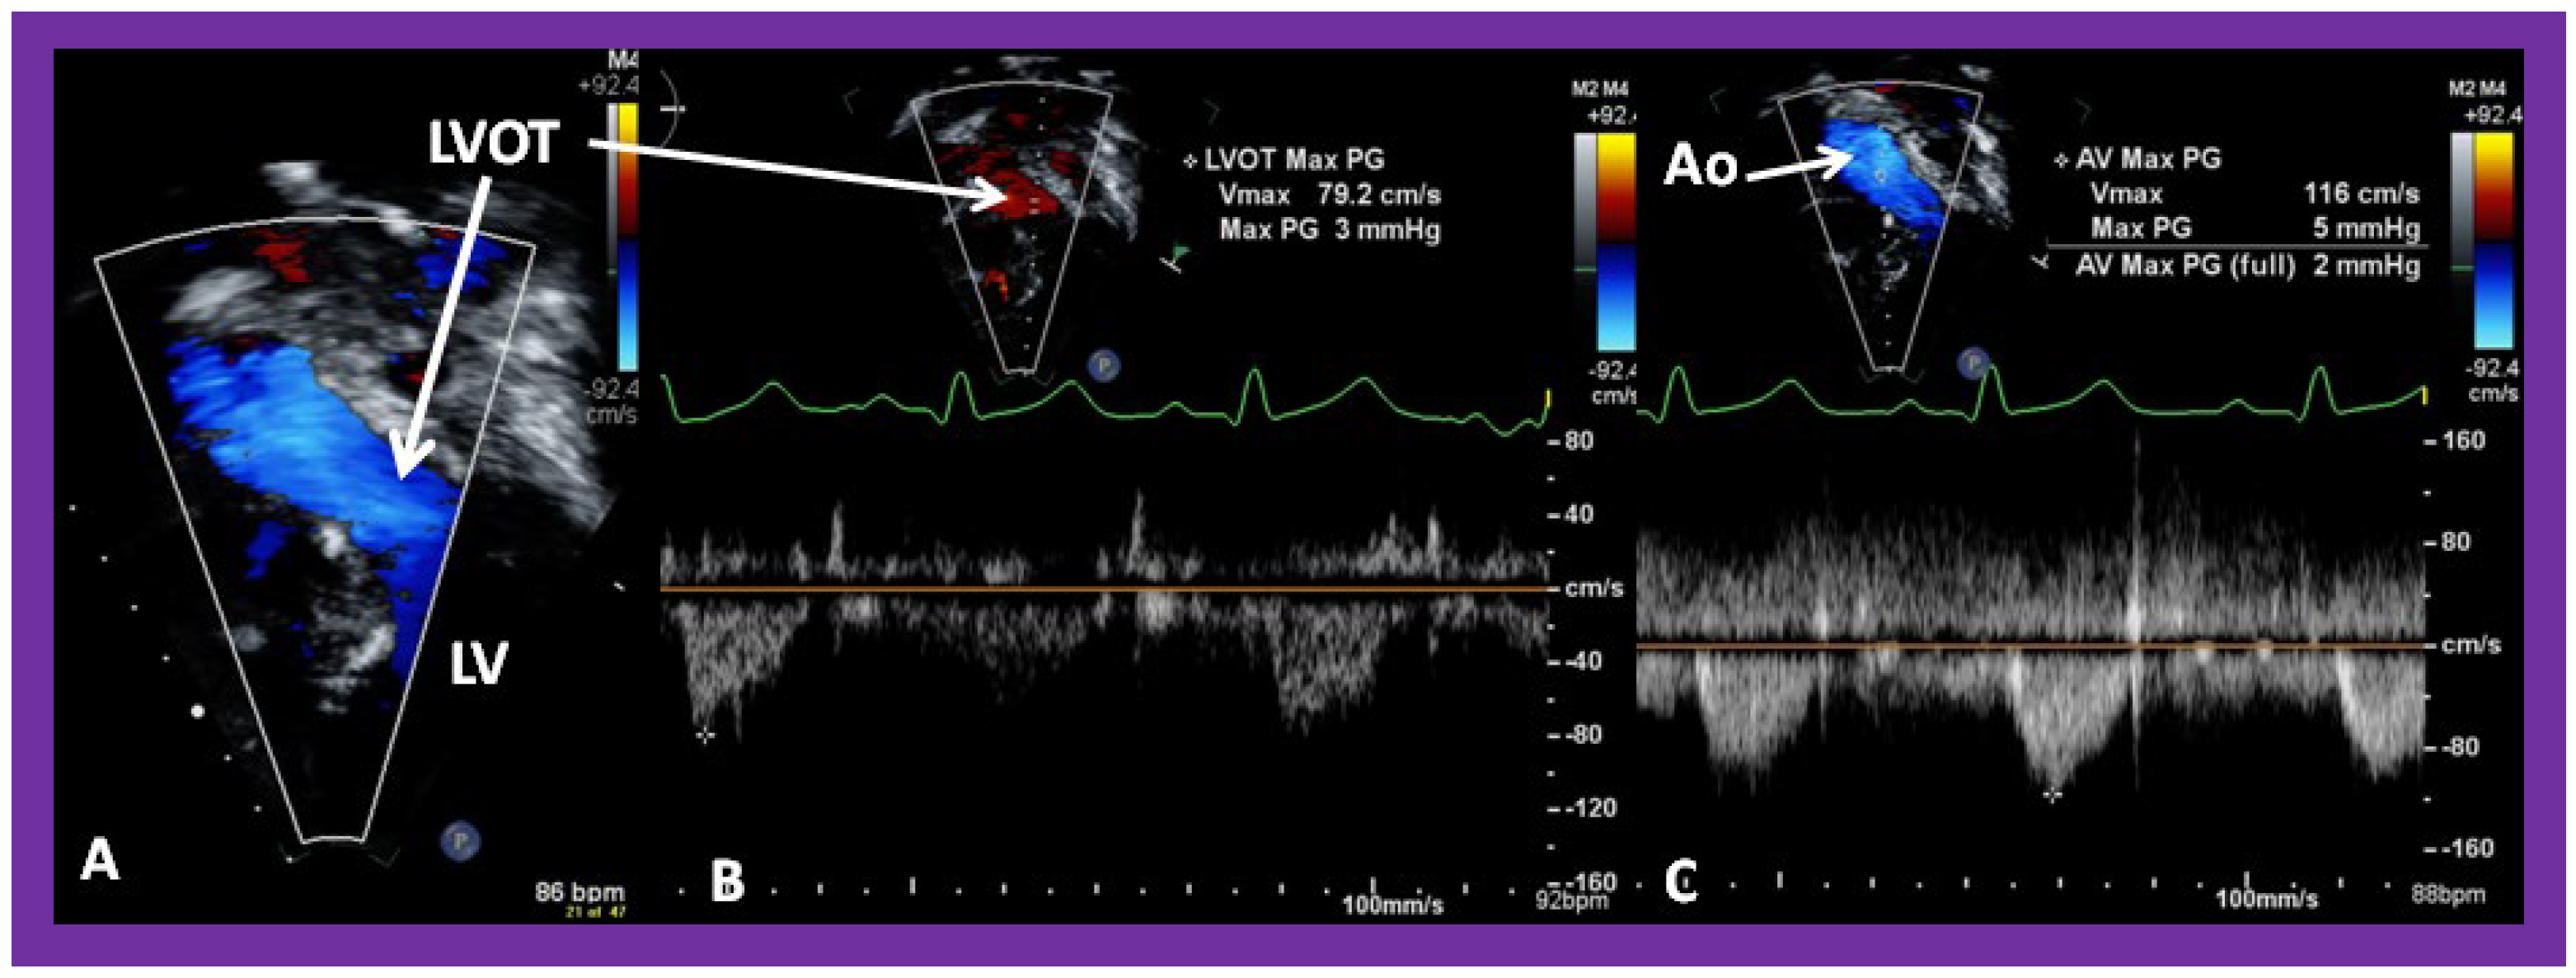

The LA is usually normal in size (Figure 38, Figure 39 and Figure 40) and empties into the LV; laminar flow across the mitral valve (Figure 41A) can be seen. Drainage of all four pulmonary veins into the LA may be demonstrated by color flow mapping in multiple echocardiographic views. The LV is either normal in size or slightly dilated. In type I patients with normally related great arteries, the LV outflow into the aorta is demonstrable on echo-Doppler with laminar, unobstructed flow with near normal (~1.0 m/s) Doppler flow velocity (Figure 41B and Figure 42). The RV is small and hypoplastic (Figure 39 and Figure 40). If the VSD has already spontaneously closed (Figure 40), the RV has no communication with any other structures since the connection with the PAs has been severed during bidirectional Glenn or Fontan procedures. If the VSD did not undergo spontaneous closure, the RV forms a cul-de-sac connection with the LV (Figure 39 and Figure 43). In Type I patients with atresia of both tricuspid and pulmonary valves (Type Ia), the hypertrophied RV may protrude into the LV outflow region (Figure 44). However, there is usually no evidence for obstruction across this region (Figure 45).

Figure 41. Selected video frames from an apical views demonstrating laminar flow from the left atrium (LA) to the left ventricle (LV) (A) and from the LV to aorta (Ao) (B). Note laminar flow in the LV outflow tract (LVOT) (B). Medial portion of the conduit (C) is seen in (A).

Applsci 11 09472 g041

Figure 42. Selected video frames from an apical view demonstrating laminar flow from the left ventricle into the aorta (Ao). Note laminar flow in the LV outflow tract (LVOT) and low Doppler flow velocity (~0.8 m/s).

Applsci 11 09472 g042